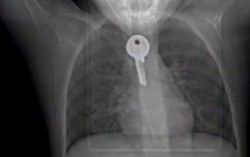

Bé 6 tuổi nhập viện cấp cứu vì nuốt chìa khóa

Phòng & chữa bệnh 21:45 13/02/2019Khi đang chơi trong nhà thì nhặt được chiếc chìa khóa và vô tình nuốt phải. Bé sợ bố mẹ mắng nên không dám nói ra. Sau đó, bé khó nuốt, ăn vào bị nôn nên gia đình đưa đến BV cấp cứu.